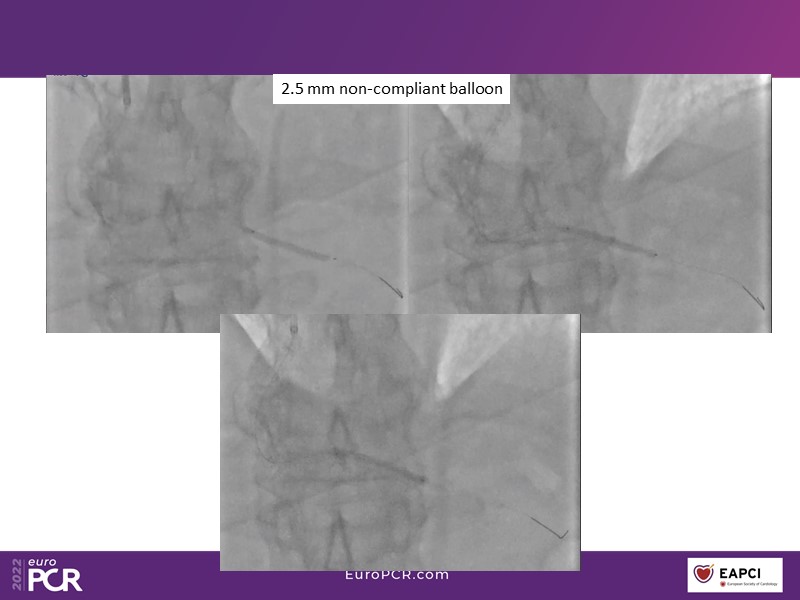

Alexandre Abizaid, Marco Valgimigli, Fazila Malik, Luca Testa, Patrick W. Serruys, Damiano Regazzoli, Kumar Prathap, and Sandeep Basavarajaiah take turns in this session to discuss two innovative technologies: a stent platform with nanotechnology and a novel drug-coated balloon (DCB). These novel technologies both have unique features that could change daily practice and improve outcomes.

- To find out more about the application and mechanism of a sirolimus coated balloon for coronary artery disease treatment with case presentations in complex settings

- To understand how useful is a DES and DCB stent platform in complex coronary artery disease settings with case demonstrations and follow-up in diabetes mellitus